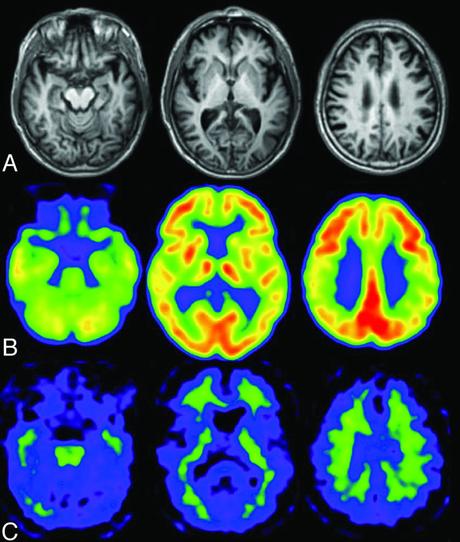

A los pocos minutos de comenzar el ejercicio, la actividad neuronal ilumina tu cerebro como una máquina tragamonedas que también mejora tu estado de ánimo.